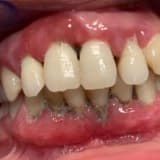

Kanama, kızarıklık ve şişlik dişeti hastalığının çarpıcı belirtileridir. Dişeti hastalığında; çene kemiğinin erimesi sonucu dişlerin sallanmasına kadar geçen süreçte en rahatsız edici dolayısıyla da en dikkat çekici belirti kanamadır. Bu nedenle de dişeti kanaması çok ciddiye alınmalı ve görüldüğü anda takip edilerek doktora gidilmelidir.